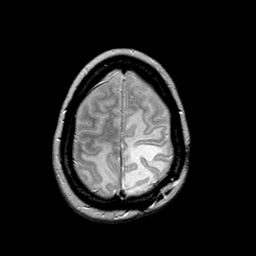

MR Study #2 -- Slice #43

[Home][Help][Clinical][Tour 1][Tour 2][Tour 3] Slice 43